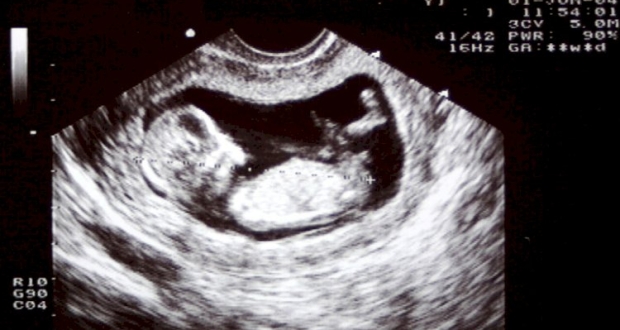

استغرب رجل من أهالي مدينة أوفا الروسية كثيرا حين طالع تقريرا طبيا من المستشفى سجل فيه تشخيص أنه حامل.

ونشر الرجل صورة فوتوغرافية لصفحة من التقرير الطبي المذكور في حسابه على شبكة التواصل الاجتماعي الروسية VK ، ما أثار ضجة ضمن مستخدميها. وأفاد الرجل بأن التقرير يضم توصية بزيارة عيادة طبيب الأمراض النسائية.